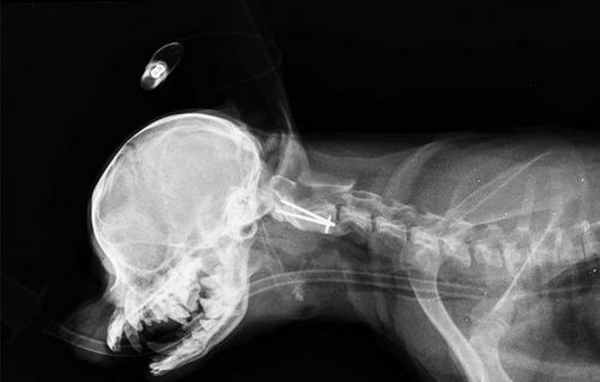

Интраоперационное - вентральная фиксация спицами Киршнера первого и второго шейного позвонка.

Укрытие металла костным цементом